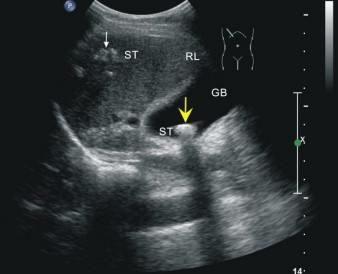

這位先生姓錢,自訴飲酒后出現胸骨后疼痛4小時,呈壓榨性,持續(xù)不緩解,伴大汗、面色蒼白、惡心、欲吐,既往無高血壓、糖尿病、冠心病病史,吸煙史30年,偶有飲酒,入院時查體血壓為120/80mmHg,心率:98次/分,節(jié)律規(guī)整,未聞及明顯雜音。心電圖:竇性心律,心率98次/分,II、III、aVF導聯病理性Q波,ST段下移,不正常心電圖。不除外急性心肌梗死。急檢心肌酶及超敏肌鈣蛋白、淀粉酶,結果回報心肌酶、超敏肌鈣蛋白無明顯改變。疼痛時復查心電圖較前無變。胸痛癥狀仍持續(xù)不緩解,給予曲馬多止痛不改善。請示李桂武主任醫(yī)師,主任給予詳細詢問病史、癥狀及查體,患者膽囊區(qū)有壓痛無反跳痛,考慮患者可能存在膽囊性疾病,不排除腎結石,指示:急檢肝膽胰脾彩超及泌尿系彩超。我急忙陪著患者及家屬去門診彩超室做肝膽胰脾及泌尿系彩超。結果如下圖。提示膽囊結石。

請肝膽外科梁博主任會診后建議行CT檢查以進一步明確診斷,肝膽胰脾CT結果可見膽囊不大,內見高密度結節(jié),約10mm(IM33),膽總管無擴張。建議轉入肝膽外科行手術治療。